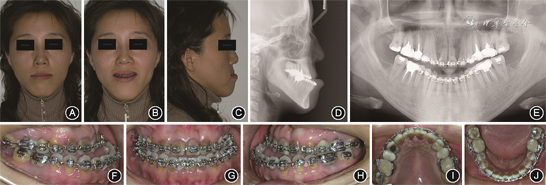

成年患者正颌术前面像、口内像和影像学资料 A:正面像;B:正面微笑像;C:侧面像;D:头颅侧位X线片;E:曲面体层X线片;F:右侧

像;G:正面

像;H:左侧

像;I:上颌

面像;J:下颌

面像

面像(2)正颌手术:正颌手术采用双颌手术。上颌行Le Fort Ⅰ型截骨术,前徙上颌骨,于双侧梨状孔边缘和双侧颧牙槽嵴处分别以2块“L”型微型钛板、8枚微型螺钉固定。下颌行双侧矢状劈开截骨后退术,于双侧外斜线处以2块小型钛板、8枚微型螺钉固定。

(3)术后正畸治疗:正颌术后2个月,尖牙、磨牙基本为远中关系,前牙覆

覆盖较浅,行双侧Ⅲ类颌间牵引,维持上下牙咬合关系;术后5~6个月,双侧前牙区及磨牙区行颌间“8”字牵引,调整咬合关系(图5);术后7~12个月,33—43邻面去釉3次,斜行牵引调整中线,颌间弹力牵引调整咬合关系,使用摇椅弓改善覆

覆盖关系;术后13个月(矫治28个月),牙齿排列整齐,咬合关系正常,拆除固定矫治器,上下颌戴压膜保持器(图6)。